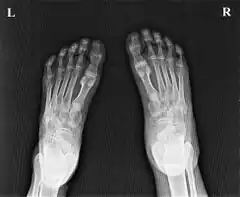

| Ainhum of the left foot of a Zulu patient in Ngwelezane Hospital, KZN, South Africa.(The little toe on the opposite foot had auto-amputated several years earlier.) | |

Imaging

Soft tissue constriction on the medial aspect of the fifth toe is the most frequently presented radiological sign in the early stages. Distal swelling of the toe is considered to be a feature of the disease. In grade III lesions osteolysis is seen in the region of the proximal interphalangeal joint with a characteristic tapering effect. Dispersal of the head of the proximal phalanx is frequently seen. Finally, after autoamputation, the base of the proximal phalanx remains. Radiological examination allows early diagnosis and staging of ainhum. Early diagnosis is crucial to prevent amputation. Doppler shows decreased blood flow in posterior tibial artery.